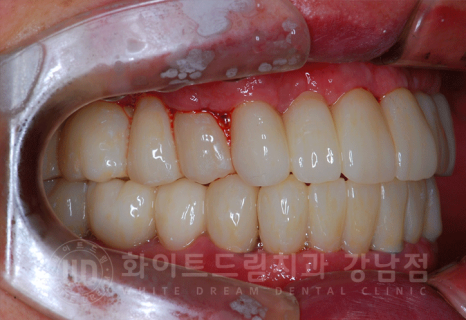

총 치료 기간 2017.06.03 - 2018.02.21 8개월 소요.

동일 인물이며 동일 환경에서 촬영되었습니다.

전악 임플란트는 낮아진 교합을 다시 설정하는 교합 거상술이 필요하기 때문에

보통 1년 정도의 기간을 두고 치료를 진행합니다.

치주염이 심해 거의 모든 잇몸뼈에 염증이 있는 상태였는데

3D CT를 통해 단단한 잇몸뼈 부위를 찾아 식립했으며, 1년 이내의 치료 기간이 소요되었습니다. ^^

환자분도 치료 기간 내내 적극적인 협조를 해주셔서 보다 빠르게 치료가 완료된 것 같습니다.